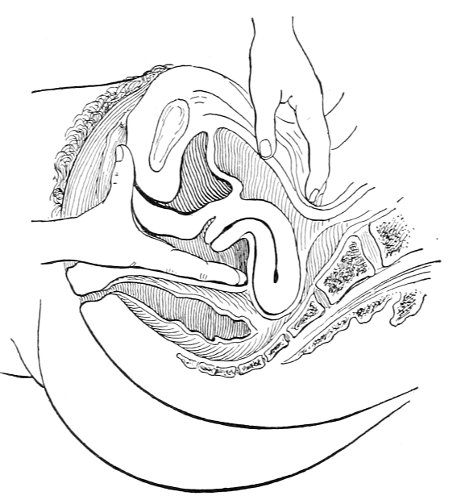

Vaginal and Bimanual Examination.—Having examined and noted the condition of the external genitals, the physician should next proceed to examine the vagina. The index finger of the right or the left hand should be gently introduced into the vagina. The condition of the vaginal walls, and the direction, consistency, form, etc. of the vaginal cervix, may be determined. The shape and size of the os uteri should be noted. The ulnar edge and the tips of the fingers of the other hand should then be placed upon the abdomen, immediately above the symphysis pubis, and gently pressed backward and downward toward the vaginal finger 24 (Fig. 2). In this way the various pelvic organs, the uterus, Fallopian tubes, ovaries, and ureters, may be palpated between the two hands, and their position, size, shape, and consistency may be determined. Such an examination is, of course, made much more easily in a thin woman than in a fat one. A thin woman a few weeks after labor may be examined most easily, on account of the relaxation of the abdominal and vaginal walls.

This is called the bimanual method of examination, and the student will find that as he acquires practice in this method he will gradually depend less upon examination by the uterine sound and the speculum, and will rely altogether upon his sense of touch, his ability to palpate.

In making the bimanual examination the structures 25 should be palpated methodically in order. The vaginal finger notes the condition of the cervix uteri. If the fundus be in the normal position, the uterus can then be taken between the abdominal hand (upon the fundus) and the vaginal finger (upon the cervix) (Fig. 3). The shape, size, mobility, and consistency are noted. The vaginal finger is then passed anteriorly and laterally toward either uterine cornu, while the abdominal fingers pass over to the posterior aspect of the same cornu. The ovarian ligament and the proximal end of the Fallopian tube may thus be felt. Passing farther outward, the whole of the tube and the ovary may be examined. The same procedure is then applied to the opposite side.